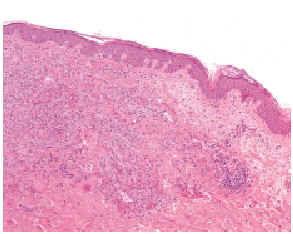

El estudio histológico, tanto de las lesiones sésiles como de las pediculadas, reveló la existencia de una epidermis adelgazada y de un tumor dérmico de células fusiformes (figs. 1 y 2) que rodeaban estructuras vasculares rudimentarias, con extravasación de hematíes y células plasmáticas. Asimismo, se observaron numerosas figuras mitóticas. El estudio inmunohistoquímico reveló positividad para FVIII, CD34 y CD31.

Fig. 2.--Epidermis normal con desarrollo de una tumoración de células fusiformes que ocupa toda la dermis (HE, ×40).